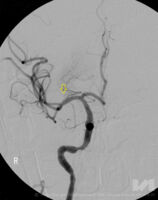

Hier besteht bei einem Teil der Patienten die Möglichkeit, das Blutgerinnsel mechanisch mittels eines Katheters - ähnlich dem Herzkatheter - zu entfernen: Das Gerinnsel wird direkt über ein Maschengitter (ein 4-6 mm großer sog. Stent) herausgezogen oder abgesaugt. „Katheter werden - innerhalb der ersten 6 Stunden nach dem Schlaganfall - mittels eines Microkatheters über die Leiste bis in das Gehirn des Patienten vorgeschoben, und zwar an jene Stelle, an welcher das Blutgerinnsel (Thrombus) die Schlagader im Hirn verstopft. Dort wird der Stent geöffnet, das Gerinnsel bleibt im feinen Metallnetz hängen und kann mittels Katheter herausgezogen und aus dem Körper entfernt werden (= Ektomie - Herausschneiden, Herausholen)“, führt der interventionelle Radiologe OA Dr. Thomas Haglmüller, Experte in der interventionellen Behandlung von Schlaganfällen, aus. Die Thrombektomie ist somit eine mechanische Methode, um die Gefäße zu eröffnen. Eine Behandlung kann zwischen 30 Minuten und 2 Stunden dauern. Dieses Vorgehen ist durch Studien bestätigt worden. Voraussetzungen, um eine Thrombektomie durchführen zu können, ist neben der Größe des Gerinnsels aber auch seine Lage: Die Therapie ist nur dann anwendbar, wenn das Gerinnsel die größeren Arterien im Gehirn verschließt - sie ist somit nicht für alle Hirnregionen geeignet. „Mit der Thrombektomie können wir große Gefäße im Gehirn schneller und vor allem effizienter eröffnen, um die Schädigung zu verringern“, erklärt Dr. Haglmüller. Seit 2 Jahren steht Schlaganfall-Patienten in Vorarlberg diese neue Behandlungsmethode zur Verfügung, insgesamt werden jährlich 40-50 Patienten mittels dieser Methode erfolgreich behandelt. Wichtig ist, dass die Betroffenen rechtzeitig bzw. ohne Verzögerung ins Zentrum gebracht werden. Nur so haben sie eine Chance!